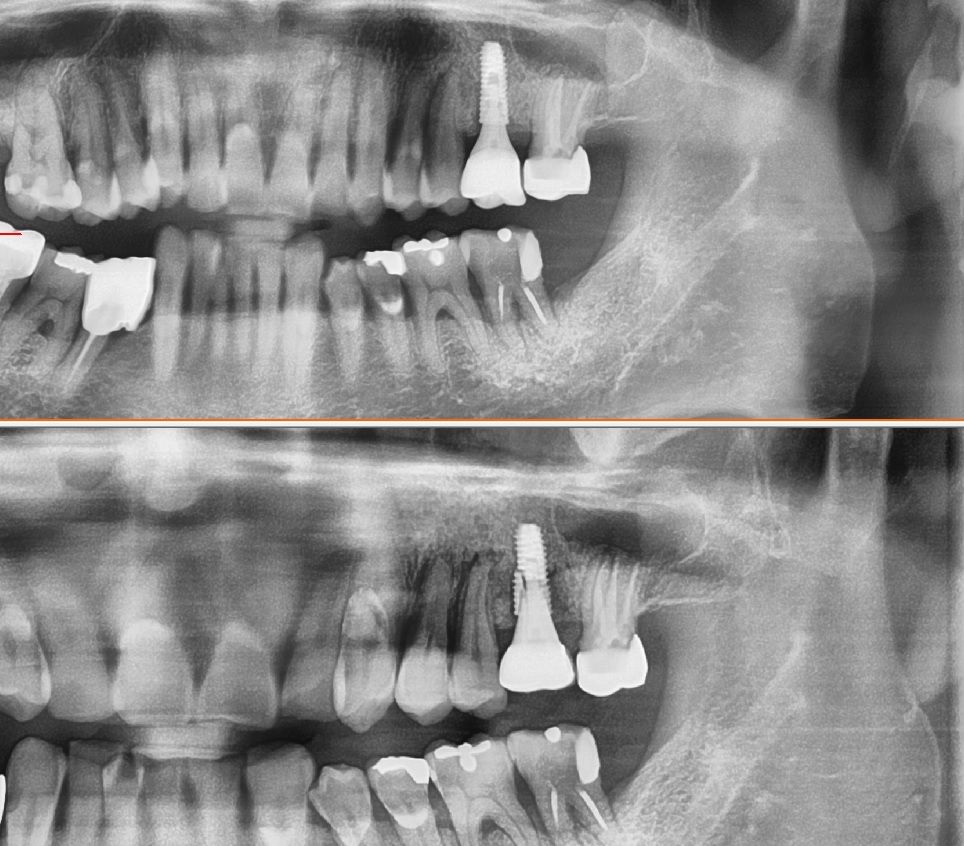

몇년전 다른 치과에서 임플란트를 시술하시고

임플란트가 흔들린다는 증상으로 저희 병원에 내원하시었습니다

환자분과 대화를 하면서

왜 하신곳에 다시 가지 않으시냐 물으니

병원이 없어졌다고 하더라구요

요즘 상담을 하면 이런 공장형 치과에서 시술을 받으시고

탈이 나서 오시는 경우가 많이 있습니다

사진을 보면 무엇이 보이시나요

바로 임플란트가 파절이 일어났습니다

여기서 임플란트가 왜 파절이 일어났을까요

왜 임플란트가 파절 즉 부러졌을까요

여기에 대한 대답은 간단합니다

씹는 저작력에 비하여

임플란트의 사이즈를

얇은 사이즈 즉 작은 사이즈를 심어서 그런것입니다

대구치 사람이 저작하는 가장 큰 힘을 받는

최후방 치아의 경우

임플란트의 직경 최소 4.5mm이상의 임플란트

식립이 지켜야 하는 원칙입니다

하지만 이 환자분은 4.0 직경의 임플란트가 식립이 되었는데요

그렇다면 여기서 궁금한점은

왜 4.0직경의 얇은 임플란트를 심었을까요?

그 이유는 치조골 직경이 얇은

부분에 치조골 이식없이

얇은 임플란트를 심었기 때문입니다

자세히 설명을 하면

치조골 직경이 좁으면 좁은 치조골에 충분한 뼈이식을 해서

치조골을 넓히고 직경이 굵은 5.0임플란트를 심어야만 합니다

하지만 치조골 이식 없이

그냥 얇은 뼈에 얇은 임플란트를 심은것이지요

다른 케이스를 한번 보겠습니다

이번 케이스도 역시나 후방 대구치인데 불구하고

저렇게 얇은 임플란트를 심고

결국은 임플란트의 파절로 이어졌습니다

그리고 나서 저희 병원에서 치조골 이식을 받으신 후

직경이 굵은 임플란트를 식립하는 수술을 받으신 케이스입니다